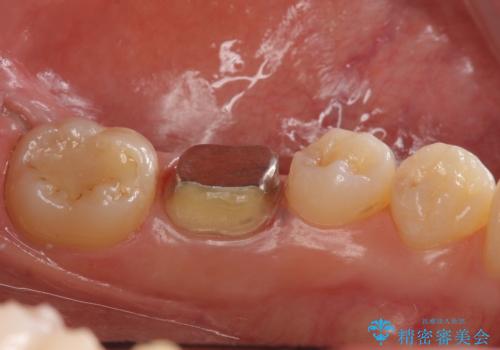

- 右下の奥歯に入れた銀歯を白くしたいとのことで来院されました。

根っこの治療がされていますが、症状もなくレントゲン画像で病変も確認できないため根管内には触れず被せ物のやり替えのみとなりました。

- 右下6 仮歯+セラミッククラウン 11000円+110000円費用は治療当時の料金となります